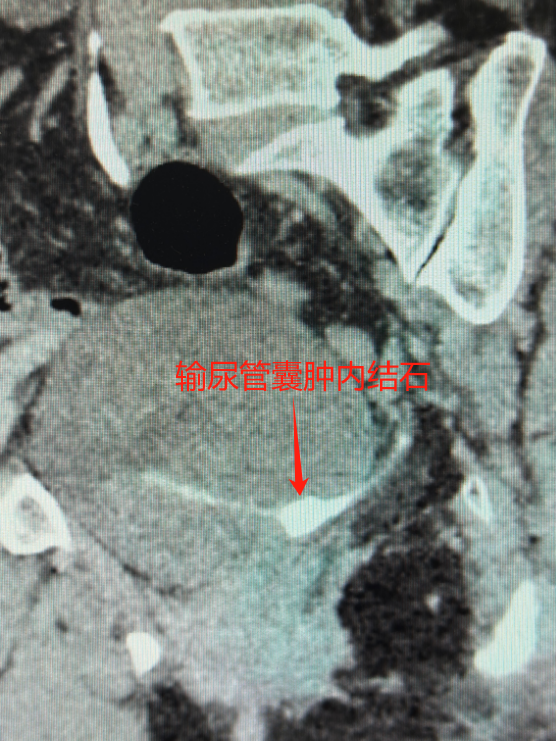

“别担心,我们一定会查清楚。”谷现恩安抚患者后,立即启动精细化诊疗流程。增强CT三维重建检查揭示真相:患者并非单纯输尿管结石,而是罕见的输尿管囊肿合并结石。这种仅占泌尿疾病1%-2%的复杂病症,临床表现与普通结石高度相似,极易误诊。谷现恩指着清晰的影像向患者解释:“囊肿就像输尿管上的‘水泡’,包裹着结石不断刺激组织,必须同步处理。”